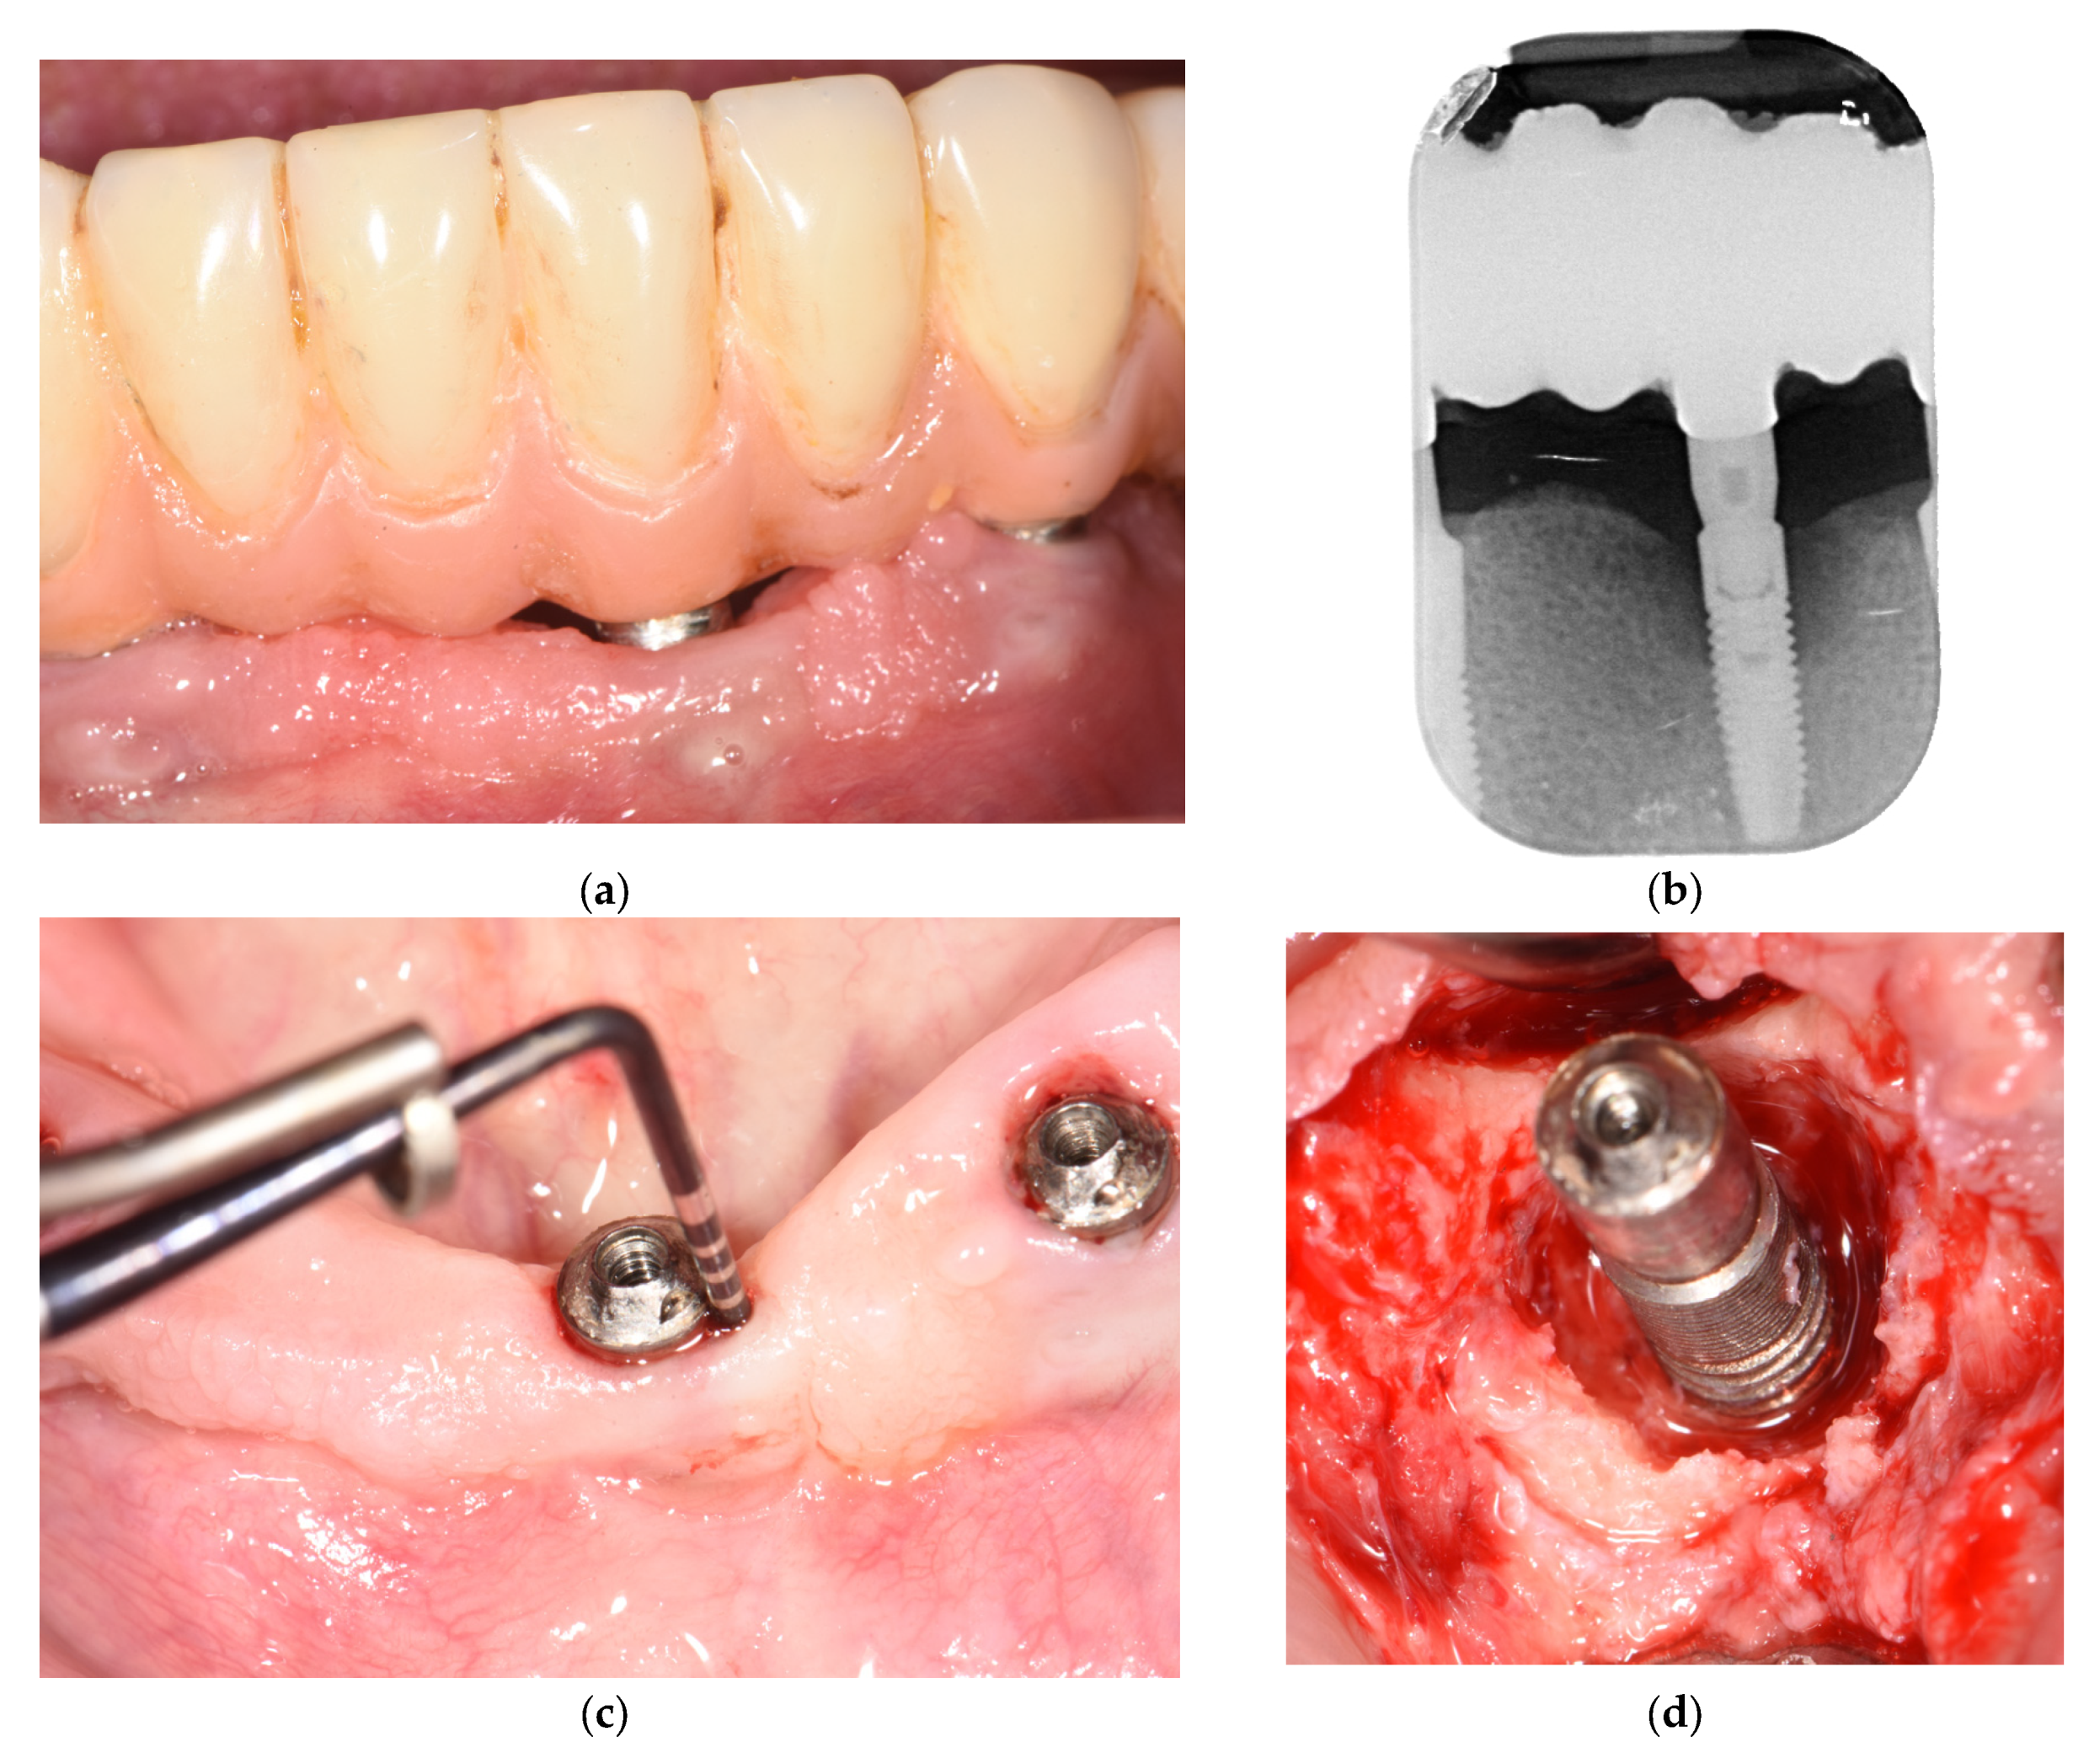

2. Materials and Methods

3. Results

- Bianchini, M.A.; Galarraga-Vinueza, M.E.; Bedoya, K.A.; Correa, B.B.; de Souza Magini, R.; Schwarz, F. Implantoplasty Enhancing Peri-implant Bone Stability Over a 3-Year Follow-up: A Case Series. Int. J. Periodontics Restor. Dent. 2020, 40, e1–e8. [Google Scholar] [CrossRef]

- Bianchini, M.A.; Galarraga-Vinueza, M.E.; Apaza-Bedoya, K.; De Souza, J.M.; Magini, R.; Schwarz, F. Two to six-year disease resolution and marginal bone stability rates of a modified resective-implantoplasty therapy in 32 peri-implantitis cases. Clin. Implant. Dent. Relat. Res. 2019, 21, 758–765. [Google Scholar] [CrossRef] [PubMed]